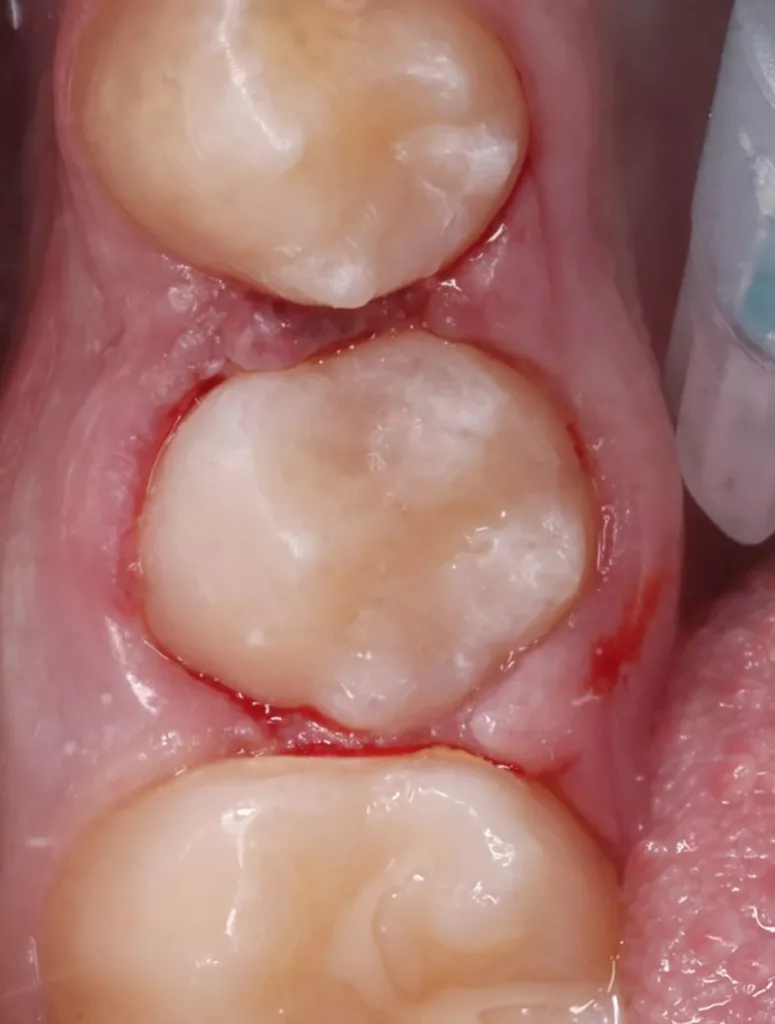

Bei routinemäßigen Röntgenkontrollen ergeben sich manchmal Zufallsbefunde unklarer Genese. So stellt sich beispielsweise bei der Betrachtung der Abbildung 1 die Frage, wie sich ein Zahnhartsubstanzdefekt so schnell entwickeln konnte. Ein weiteres Röntgenbild (Abb. 2), das vor dem Zahndurchbruch aufgenommen wurde, zeigt jedoch, dass es sich in diesem Fall nicht um Karies, sondern um die sogenannte präeruptive intrakoronale Resorption (PEIR) handelt. Für diesen Befund finden sich in der Fachliteratur auch noch andere Bezeichnungen wie „idiopathic external resorption of unerupted permanent teeth“ [1], „intra-follicular caries“ [2], „radiolucent lesions resembling caries“ [3], „occult caries“ [ 4] oder „pre-eruptive caries“ [5].

V. Slabkovskyi, O. Liutikovwährend des Durchbruchs des Zahnes 36.

Das fünfjährige Mädchen stellte sich 2017 zur jährlichen Routinekontrolle vor. Im Rahmen der Untersuchung wurden Röntgenaufnahmen der Milchmolaren gemacht (Abb. 2). Der klinische und radiologische Befund der vor uns früher gelegten Kompositfüllungen war gut, es wurde allerdings eine PEIR an den noch nicht durchgebrochenen ersten bleibenden Molaren festgestellt (Abb. 2). Den Eltern wurde empfohlen, sich unverzüglich bei Beginn des Durchbruchs der ersten Molaren erneut zur Behandlung vorzustellen. Ein Jahr später erschien die junge Patientin schmerzfrei zur Kontrolle. Der Zahn 36 war noch teilweise mit Gingiva bedeckt. Auf einer neuen Röntgenaufnahme (Abb. 1) wurde die PEIR-Läsion mit unveränderter Größe in pulpanahen Bereichen bestätigt (Grad 3 der Läsion nach Seow). Der Zahnschmelz sah intakt aus, es konnte kein pathologischer periapikaler Befund bei den noch nicht ausgewachsenen Zahnwurzeln festgestellt werden. Daraufhin wurden die verschiedenen Behandlungsmöglichkeiten von Fissurenversiegelung bis Vitalerhaltung der Zahnpulpa mit den Eltern des Kindes besprochen.